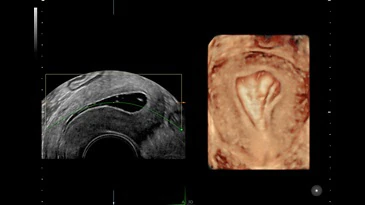

ECOGRAFIA GINECOLOGICA

Lo studio del Prof. Susini dispone di uno strumento diagnostico evoluto dotato di Intelligenza Artificiale che acquisisce immagini di altissima precisione e che permette di valutare tutti gli aspetti della salute della donna, da quelli per la prevenzione a quelli più complessi.

Il livello ottimale di imaging migliora l’affidabilità diagnostica e consente di fornire alla paziente referti ed esami efficienti, in quanto raccoglie immagini 2D, 3D e 4D con uno straordinario dettaglio clinico, fornendo una vista completa e precisa dell’anatomia, mette a fuoco anche la più minuscola struttura e permette di visualizzare le strutture vascolari dai piccoli vasi alle grandi arterie. Uno strumento così valido e all’avanguardia che ottiene in modo chiaro le immagini e le misurazioni, consente di avere la possibilità di rilevare e diagnosticare precocemente i problemi, permette lo studio NON INVASIVO di utero e ovaie per una valutazione assai precisa dei fibromi uterini dei polipi endometriali e delle malformazioni uterine ed intervenire tempestivamente con eventuali terapie, aumentando la soddisfazione e la tranquillità della paziente.